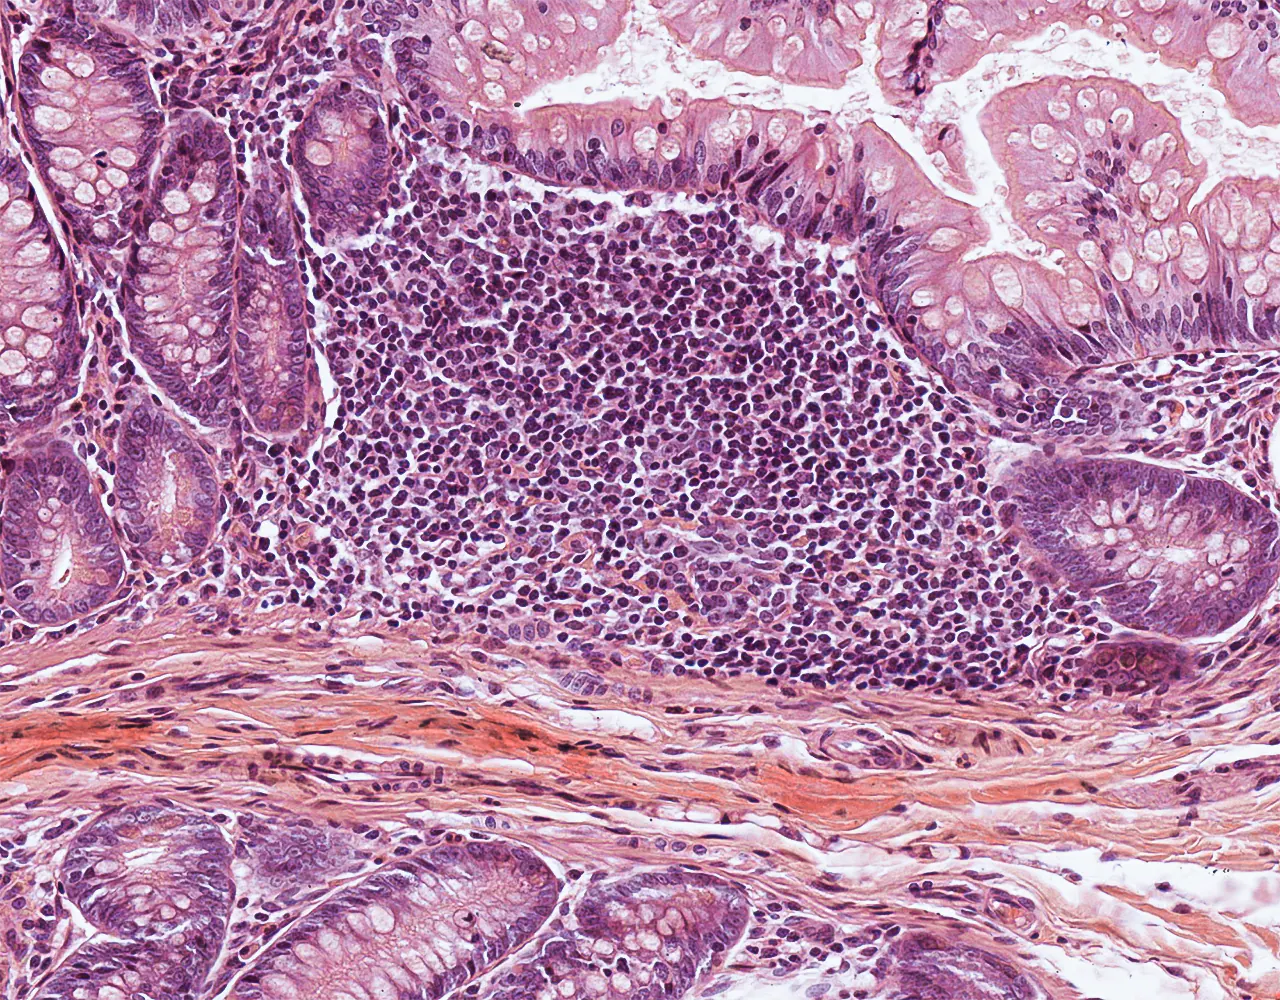

- Contribution to immune defence through gut-associated lymphoid tissue, especially Peyer patches in the ileum.

- Microscopically, the wall is composed of 4 layers from the inside outward: mucosa, submucosa, muscularis propria, and serosa.